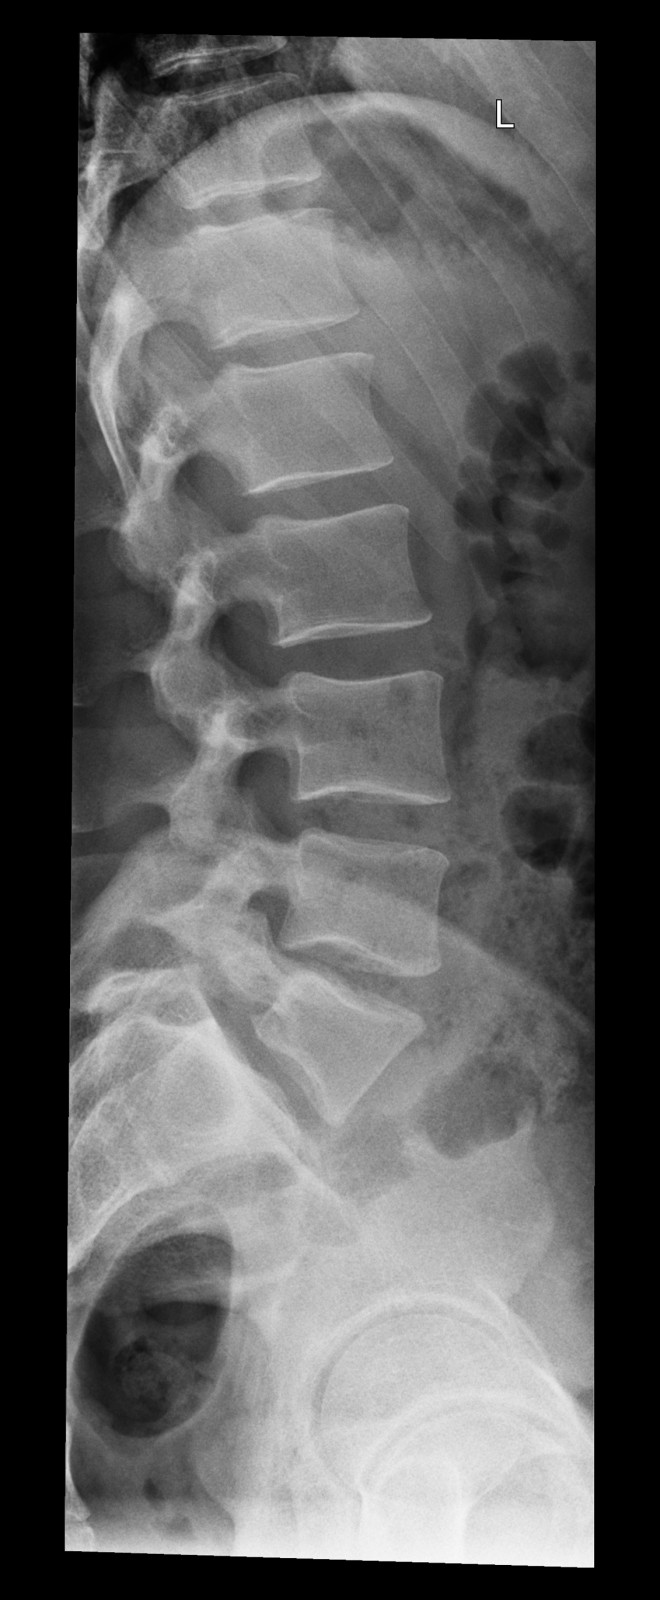

Röntgenfall des Monats Juni 2017 mit Auflösung

34 jähriger Patient mit exazerbierter Lumbago.

Beruf: Plattenleger